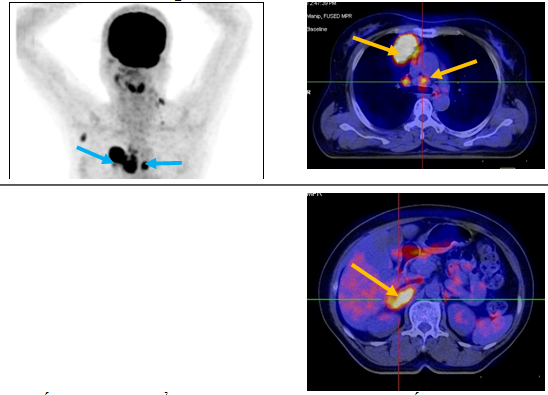

Ca lâm sàng 1: Bệnh nhân nữ, 53 tuổi, chẩn đoán: Ung thư phổi (giải phẫu bệnh: ung thư biểu mô tuyến), chụp PET/CT để xác định giai đoạn bệnh trước điều trị:

Hình 1: khối u ác tính phổi phải di căn hạch, di căn tuyến thượng thận phải (mũi tên).